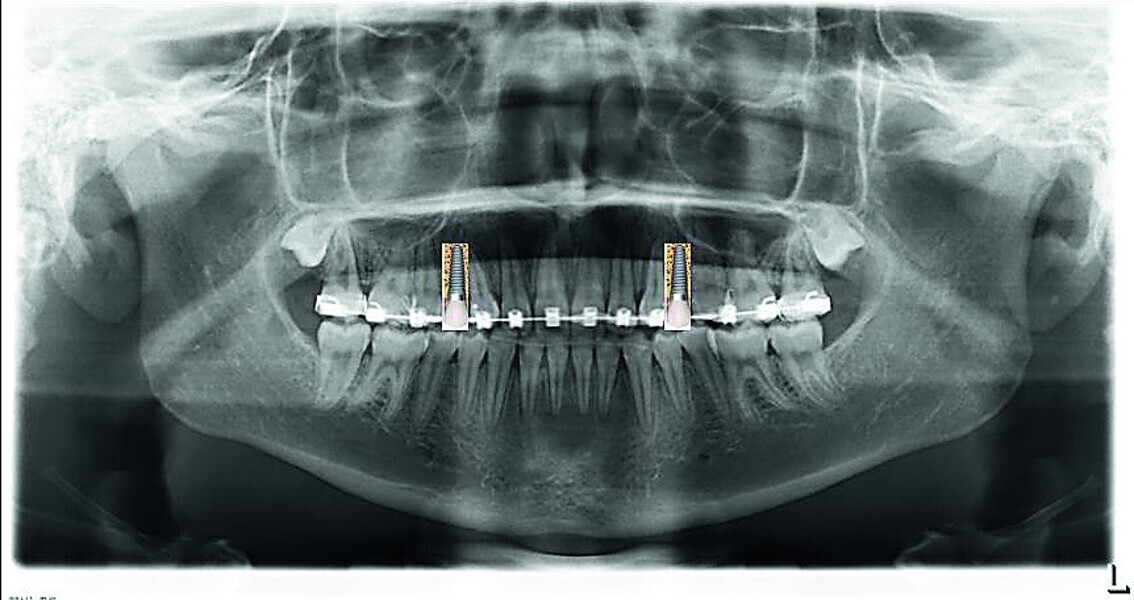

Orthodontic management of maxillary lateral incisors agenesis